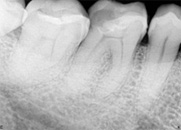

antes depois